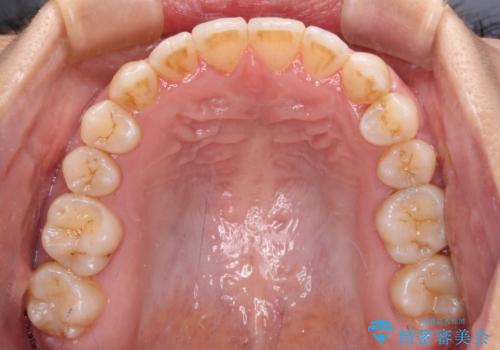

上顎の拡大に伴い反対咬合があっという間に改善されました。

元々の歯列不整は軽微であったため、僅か1年の期間で治療を終えることができました。